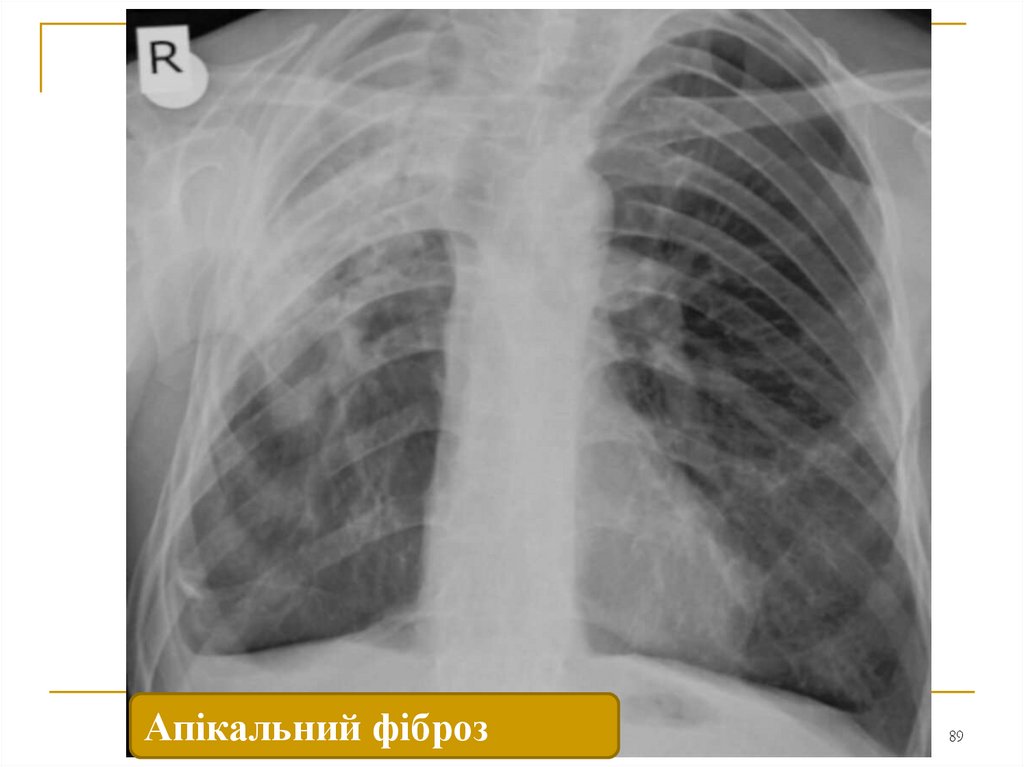

89.

Апікальний фіброз Apical lobe fibrosis

89